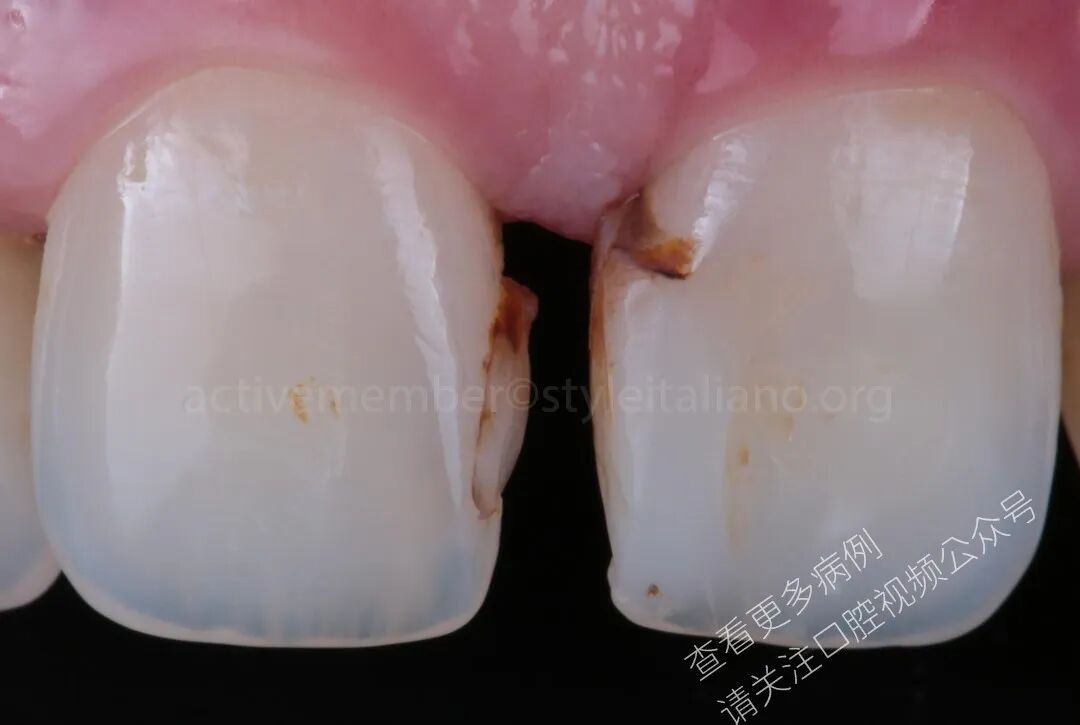

图1:口内照显示旧有复合树脂及龋坏患者就诊于本诊所,要求关闭上颌中切牙之间的牙间隙,以改善其笑容的美观性与协调性。

图2:中切牙渗透染色初诊临床情况。

图3:可见微渗漏的旧有复合树脂除患者希望关闭上颌中切牙间隙外,临床检查还发现中切牙近中区域存在旧有复合树脂修复体伴继发龋。